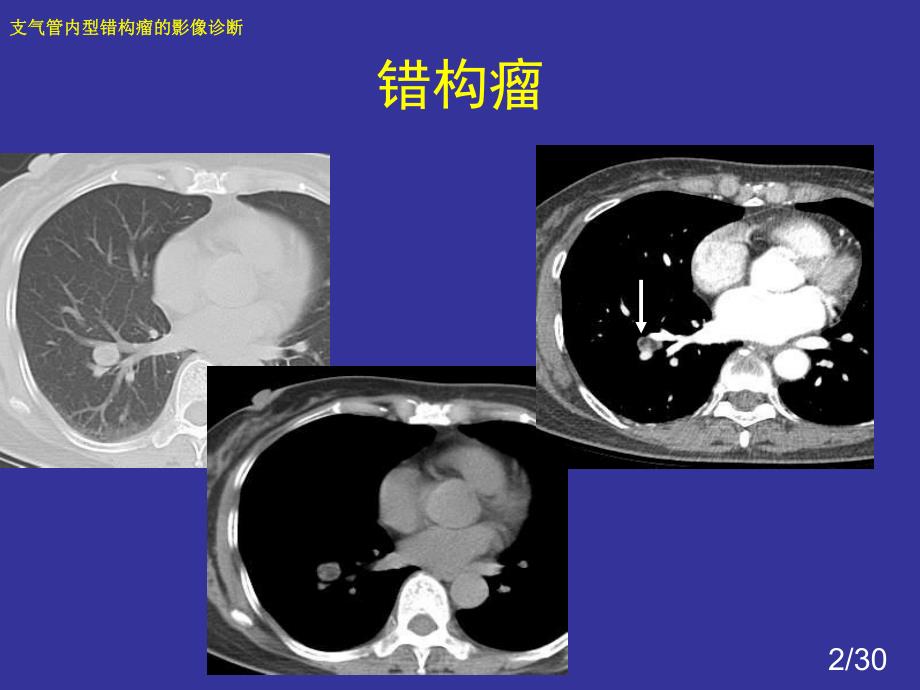

1、1/30支气管内型错构瘤的影像诊断支气管内型错构瘤的影像诊断 良性肿瘤-错构瘤2/30支气管内型错构瘤的影像诊断支气管内型错构瘤的影像诊断 错构瘤3/30支气管内型错构瘤的影像诊断支气管内型错构瘤的影像诊断 误诊中央型肺癌4/30支气管内型错构瘤的影像诊断支气管内型错构瘤的影像诊断 误诊中央型肺癌5/30支气管内型错构瘤的影像诊断支气管内型错构瘤的影像诊断 支气管内型错构瘤误诊率很高 我院共6例,误诊5例 诊断肺癌2例 诊断炎症3例 诊断支气管内良性病变1例6/30支气管内型错构瘤的影像诊断支气管内型错构瘤的影像诊断 支气管内型错构瘤误诊率很高 文献:支气管内型错构瘤4例报告及国内其他42例分

3、诊断 如何诊断?支气管内型与肺内型错构瘤是相同的肿瘤,均源于支气管黏膜下的未分化间叶组织 原始间叶组织化生形成的骨、软骨、脂肪及平滑肌等 支气管内型位于较大的支气管内,引起肺内继发改变 肺内型发生在细小支气管内,表现为肺内良性结节影 肺内型错构瘤也应看作是管内型肿瘤9/30支气管内型错构瘤的影像诊断支气管内型错构瘤的影像诊断 临床特征 本病可发生在主支气管、叶支气管及段支气管。主要由软骨和腺体组织组成,也可含有大量脂肪 可发生于任何年龄,以40-60岁居多 男女比例为24:110/30支气管内型错构瘤的影像诊断支气管内型错构瘤的影像诊断 影像学表现-11、向支气管腔内突出,表面光滑,窄基底与支

4、气管壁相连的软组织结节影,支气管壁未见明显增厚11/30支气管内型错构瘤的影像诊断支气管内型错构瘤的影像诊断 向支气管腔内突出,支气管壁未见明显增厚12/30支气管内型错构瘤的影像诊断支气管内型错构瘤的影像诊断 向支气管腔内突出,支气管壁未见明显增厚13/30支气管内型错构瘤的影像诊断支气管内型错构瘤的影像诊断 向支气管腔内突出,支气管壁未见明显增厚14/30支气管内型错构瘤的影像诊断支气管内型错构瘤的影像诊断 向支气管腔内突出,支气管壁未见明显增厚15/30支气管内型错构瘤的影像诊断支气管内型错构瘤的影像诊断 气管腺癌16/30支气管内型错构瘤的影像诊断支气管内型错构瘤的影像诊断 肺癌-支气